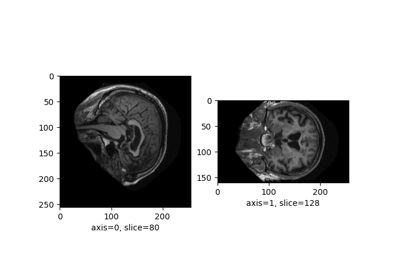

Plot a 3D image